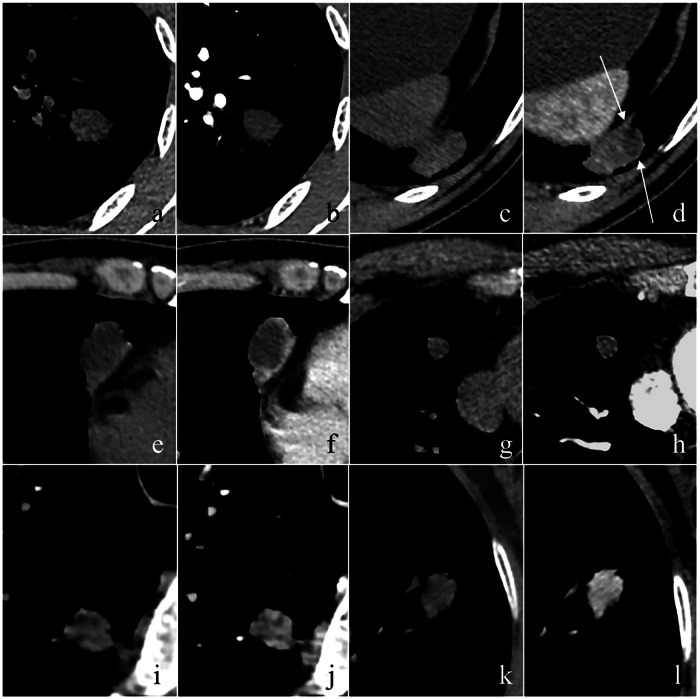

Materials and methods: From October 2019 to July 2024, 204 atypical granulomas (no calcification, satellite lesions, and/or halo sign) and 204 size-matched PLCs manifested as solid nodules (SNs) were retrospectively enrolled. Patients' clinical, as well as non-enhanced and contrast-enhanced CT data, were evaluated and compared. The enhancement patterns of lesions included no significant enhancement (▵CT value < 15 HU), rim enhancement, enhancement with well-defined necrosis, heterogeneous enhancement, and homogeneous enhancement. The latter two patterns were further divided into mild (15-29 HU), moderate (30-59 HU), and severe (≥ 60 HU) enhancement.

Key points: Atypical granulomas and PLCs exhibit high morphological similarity. Enhancement patterns of lesions are crucial for differentiating atypical granulomas and PLCs. Atypical granulomas typically display irregular shape, lower non-enhanced CT value, and non-moderate enhancement pattern. Younger age and a history of diabetes are key clinical indicators of granulomas.